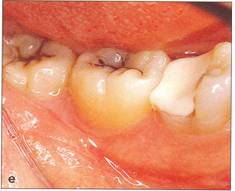

Fi 545e45f gs 5-2d and 5-2e Preoperative view of the tooth to be extracted. |

Fi 545e45f gs 5-2f and 5-29 Preoperative view of the donor tooth. |

Fi 545e45f g 5-2h Extracted donor tooth. This tooth seems to be at developmental stage 6. |

Fi 545e45f g 5-2i The recipient site right before transplant procedure (2 weeks after extraction of the first molar). |